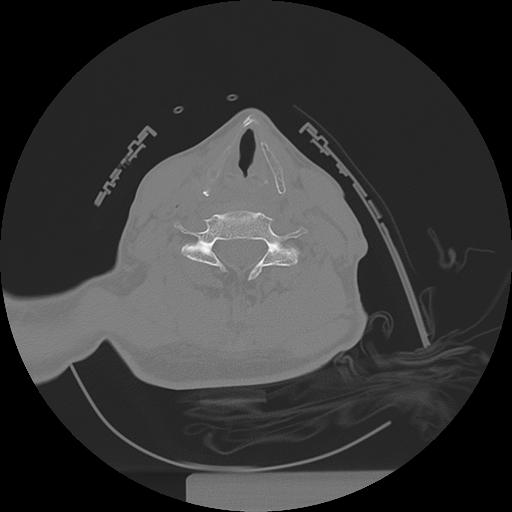

11 HUESO,,Axial,2.0,HUESO,,